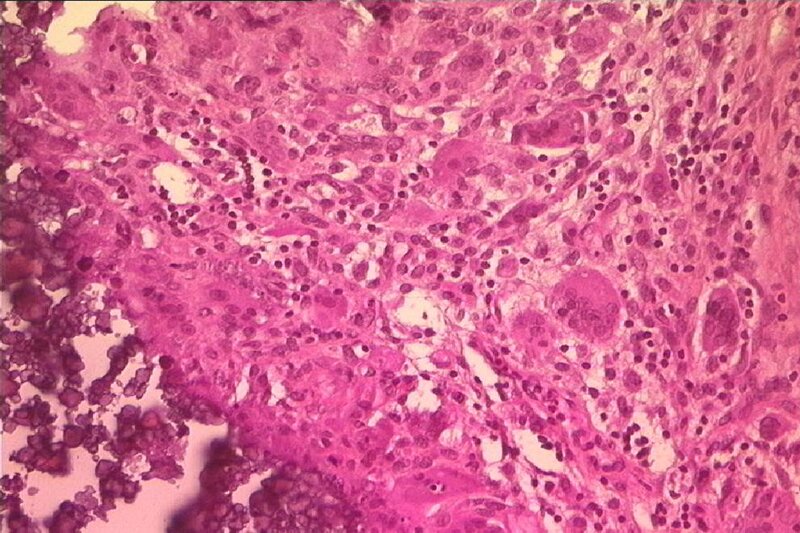

Un patient de 30 ans consultait en janvier 2003 pour une volumineuse tum?faction cervicale basse post?rieure (> 10 cm), apparue huit mois auparavant, et qui avait rapidement augment? de taille les deux derniers mois, devenant douloureuse ? l'hyperextension du rachis cervical et lors de l'antepulsion. Dans ses ant?c?dents, on notait une insuffisance r?nale chronique terminale (IRCT) en rapport avec une dysplasie r?nale kystique cong?nitale, ayant conduit ? l'h?modialyse en janvier 2002, et la notion de traumatisme cervical en septembre 2001 (chute de 10 m). A la palpation, la tumeur apparaissait ferme et fix?e au plan profond, faisant ?voquer un processus n?oplasique. Le bilan biologique objectivait?: an?mie ? 10,2 g/dl, VS ? 80, cr?atinin?mie ? 860 mmol/l, hyperphosphor?mie ? 2,4 mmol/l (N<1,4), hypercalc?mie ? 2,9 mmol/l (N<2,6), taux d'hormone parathyro?dienne ?lev? ? 624 pcg/ml (N<53), phosphatases alcalines augment?es ? 180 UI/l (N<120). L'IRM cervicale mettait en ?vidence une masse h?t?rog?ne, multiloculaire, calcifi?e, infiltrant les muscles paraspinaux avec ost?olyse de l'?pineuse de C6. Le scanner thoraco-abdomino-pelvien ?tait normal. L'examen anatomo-pathologique d'une biopsie chirurgicale de la tumeur montrait la pr?sence d'espaces pseudo-kystiques avec d?p?ts calciques ?tendus, entour?s d'une r?action granulomateuse giganto-cellulaire floride, s'associant ? une fibrose inflammatoire marqu?e, avec capillaires dilat?s, faisant le diagnostic de CPT. La nature dysm?tabolique b?nigne de la l?sion, le contexte d'IRCT avec augmentation du produit phospho-calcique et hyperparathyro?die secondaire, ont conduit ? proposer la prise en charge th?rapeutique suivante?: abstention chirurgicale, parathyro?dectomie subtotale, ?quilibre phospho-calcique (ch?lateurs du phosphore), indication prioritaire d'une transplantation r?nale.